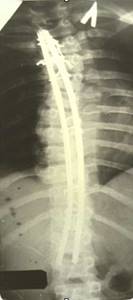

| Динамический корректор. Результат на 2-е сутки после операции |

| Результат коррекции сколиотической деформации эндокорректором с деротационными скобами |